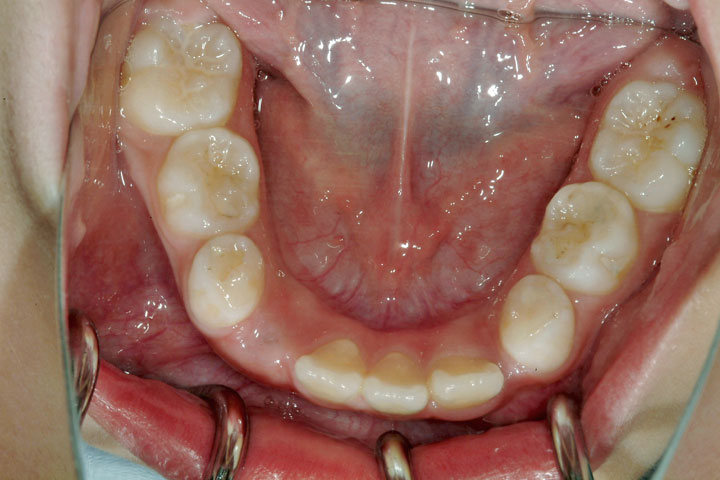

上顎前突(出っ歯)

叢生(乱ぐい歯)

欠損歯

上顎の前突感と歯列に空隙の少ないことを気にされて来院した小学校3年生の女子です。下顎前歯に一本先天性の欠損がありましたが、それでも下顎左側犬歯、上顎両側犬歯に萌出空隙がほとんどない状態で、重度の叢生が予想されました。前期治療上顎大臼歯の遠心移動のためヘッドギアーを用い、また上下顎の拡大も同時に行いました。その後永久歯への交換を待って、デーモンシステムをもちいたエッジワイズ治療に移行しております。ただし上顎については、非抜歯では歯の配列までは可能でしたが前突感が残ると判断し上顎両側小臼歯抜歯をお願いしております。エッジワイズ装置撤去後はボンデッドワイヤーとリテーナーでの保定へ移行いたしました。前期治療に約3年、エッジワイズ治療に約2年のケースとなりました。